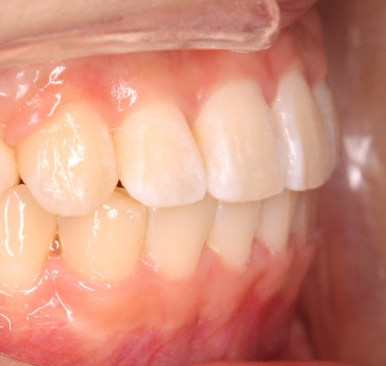

위 사진은 연산동교정치과 처음 내원하셨을 때의 입안 모습입니다. 몇 가지 모습이 관찰됩니다.

치아가 삐뚤삐뚤합니다.

위~아래 앞니가 많이 겹쳐서 아랫니가 많이 모이지 않는 "과개교합" 입니다.

앞니가 앞으로 뻐뜨러져 있습니다.